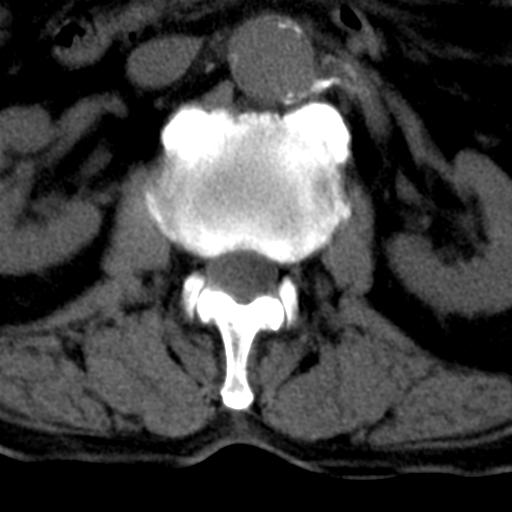

男性 82 主动脉夹层 请大家看看椎体是什么改变啊

腰椎退行性变,明显的骨赘形成,所指低密度灶为正常松质骨。